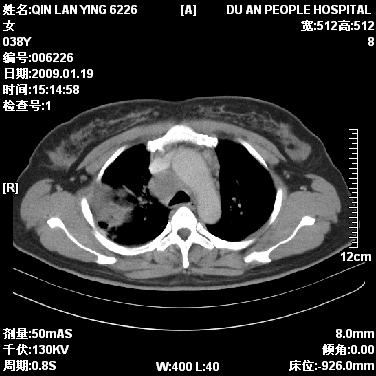

标题: CT17781:女,38岁,胸疼1个月。

女,38岁,胸疼1个月。wbc:1万4

1)右肺中央型肺癌并右肺上叶阻塞性肺炎、节段性肺不张,纵隔淋巴结转移、右侧胸膜转移、肝脏转移。2)右侧胸腔少量积液。

1、右侧中央型肺癌并阻塞性肺不张,纵隔内、主动脉弓旁、右肺门淋巴结及肝脏转移可能性大,建议纤支镜进一步检查。

2、右侧胸腔积液。

本病例有几个容易诊断的地方:1、右肺上叶前段支气管闭塞,肺不张。2、淋巴结明显肿大。3、肝脏多个类圆形低密度影呈“牛眼征”改变,高度提示转移。

从影像学角度分析      右肺上叶中央型肺癌,并阻塞性不张、肺炎,纵隔淋巴结、膈顶淋巴结转移。

肝内两个大小不等低密度结节,内可见更低密度影,首先考虑肝内转移瘤,但联想到患者wbc1万4,建议楼主还是做个增强比较明确,除外肝脓肿的可能。